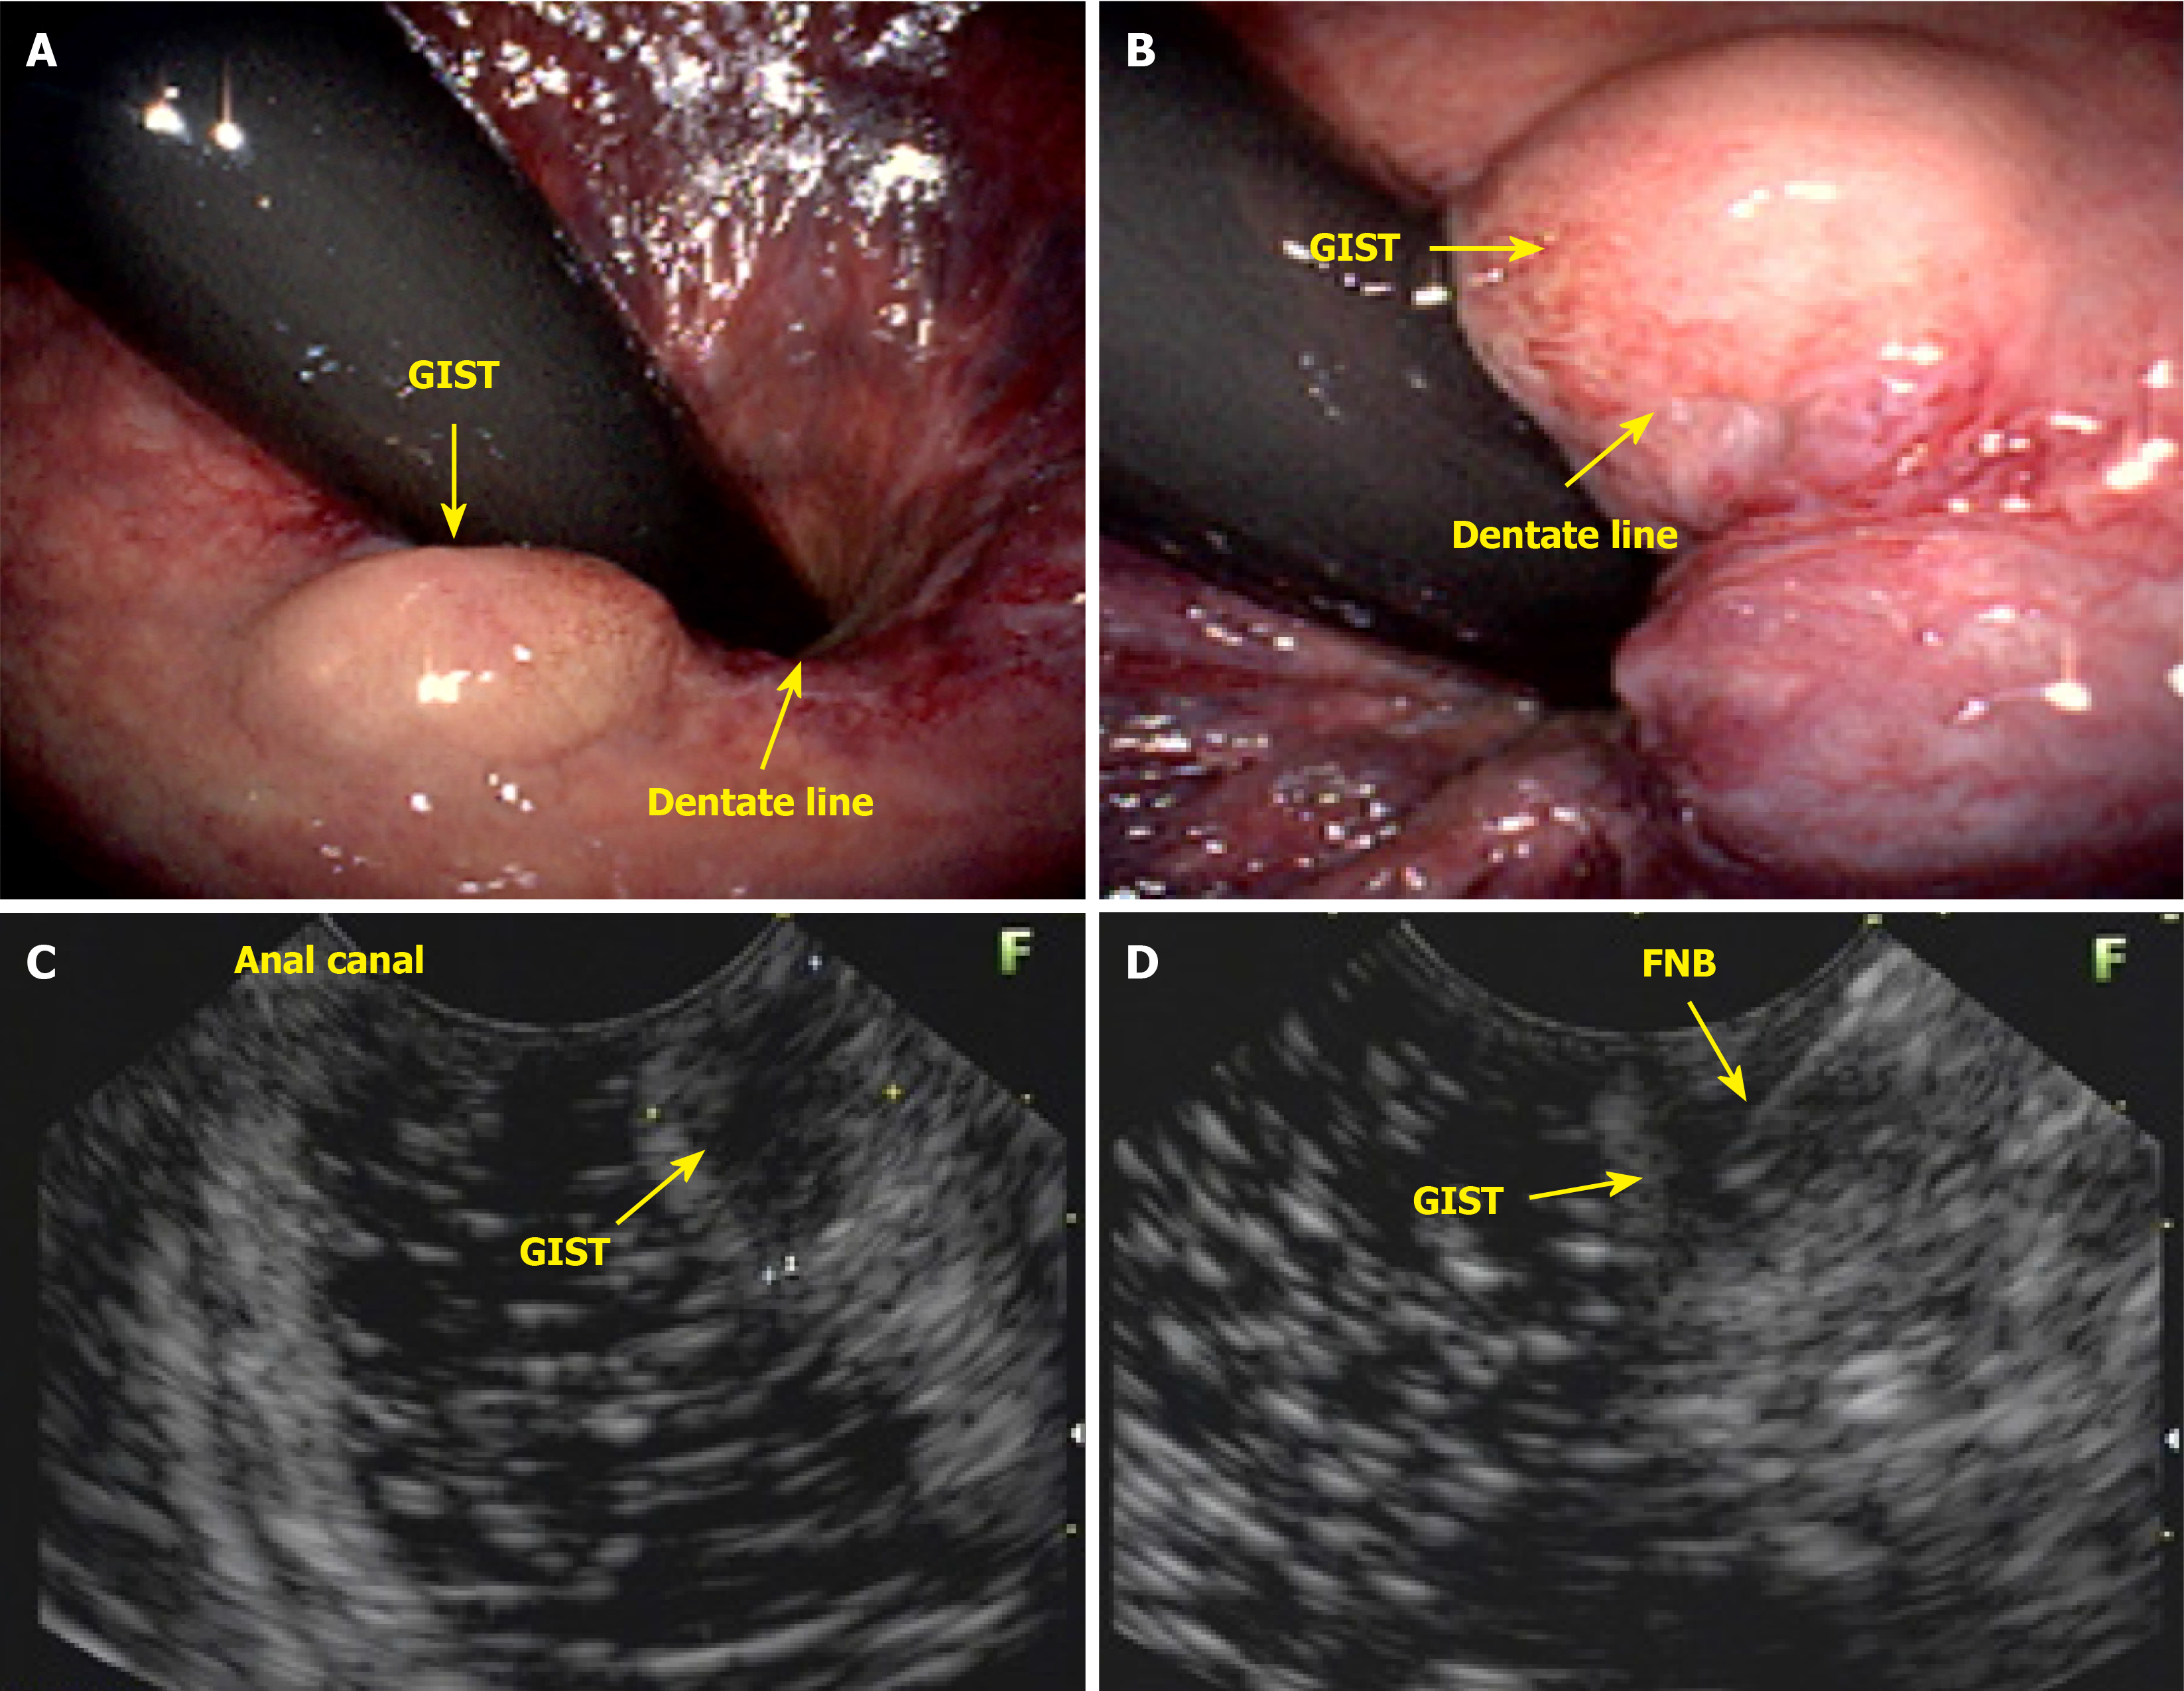

As the number of requests for colonoscopy from clinicians, gynecologists, and physicians outside the field of coloproctology continues to rise, the responsibility of diagnosing, treating, and guiding patients with anal lesions often falls to the endoscopist. In countries with limited healthcare systems, where patients face challenges accessing specialists, an endoscopist with knowledge of anal pathologies can diagnose these lesions and, in many cases, provide the necessary treatment. Furthermore, the endoscopist should remove premalignant anal canal lesions (Figure 8). Lesions in the anal canal should be biopsied or removed during colonoscopy. This patient presented with a subepithelial nodule in the anal canal, which was evaluated and biopsied via endoscopic ultrasound. Histological analysis revealed a gastrointestinal stromal tumor (Figure 9).

Diagnostic endoanal ultrasound (EAUS) offers several clinically significant benefits in the evaluation and management of anal neoplasms, particularly anal SCC. EAUS provides high-resolution, real-time imaging of the anal canal, allowing for precise assessment of tumor depth, involvement of the internal and external anal sphincters, and perirectal tissue invasion. This detailed local staging is critical for treatment planning, especially in distinguishing early-stage tumors that may be amenable to less aggressive therapy from those requiring more extensive intervention. EAUS is cost-effective, well-tolerated, and can be performed in patients with contraindications to magnetic resonance imaging, such as those with certain implants or severe claustrophobia. However, EAUS is operator-dependent and may be limited in patients with anal stenosis or extensive disease, and its ability to assess lymph node involvement is inferior to that of magnetic resonance imaging. Despite these limitations, EAUS remains a valuable tool for initial staging, treatment planning, and posttreatment surveillance in anal neoplasms, particularly when high-resolution assessment of the anal sphincter complex and local tumor extent is needed.